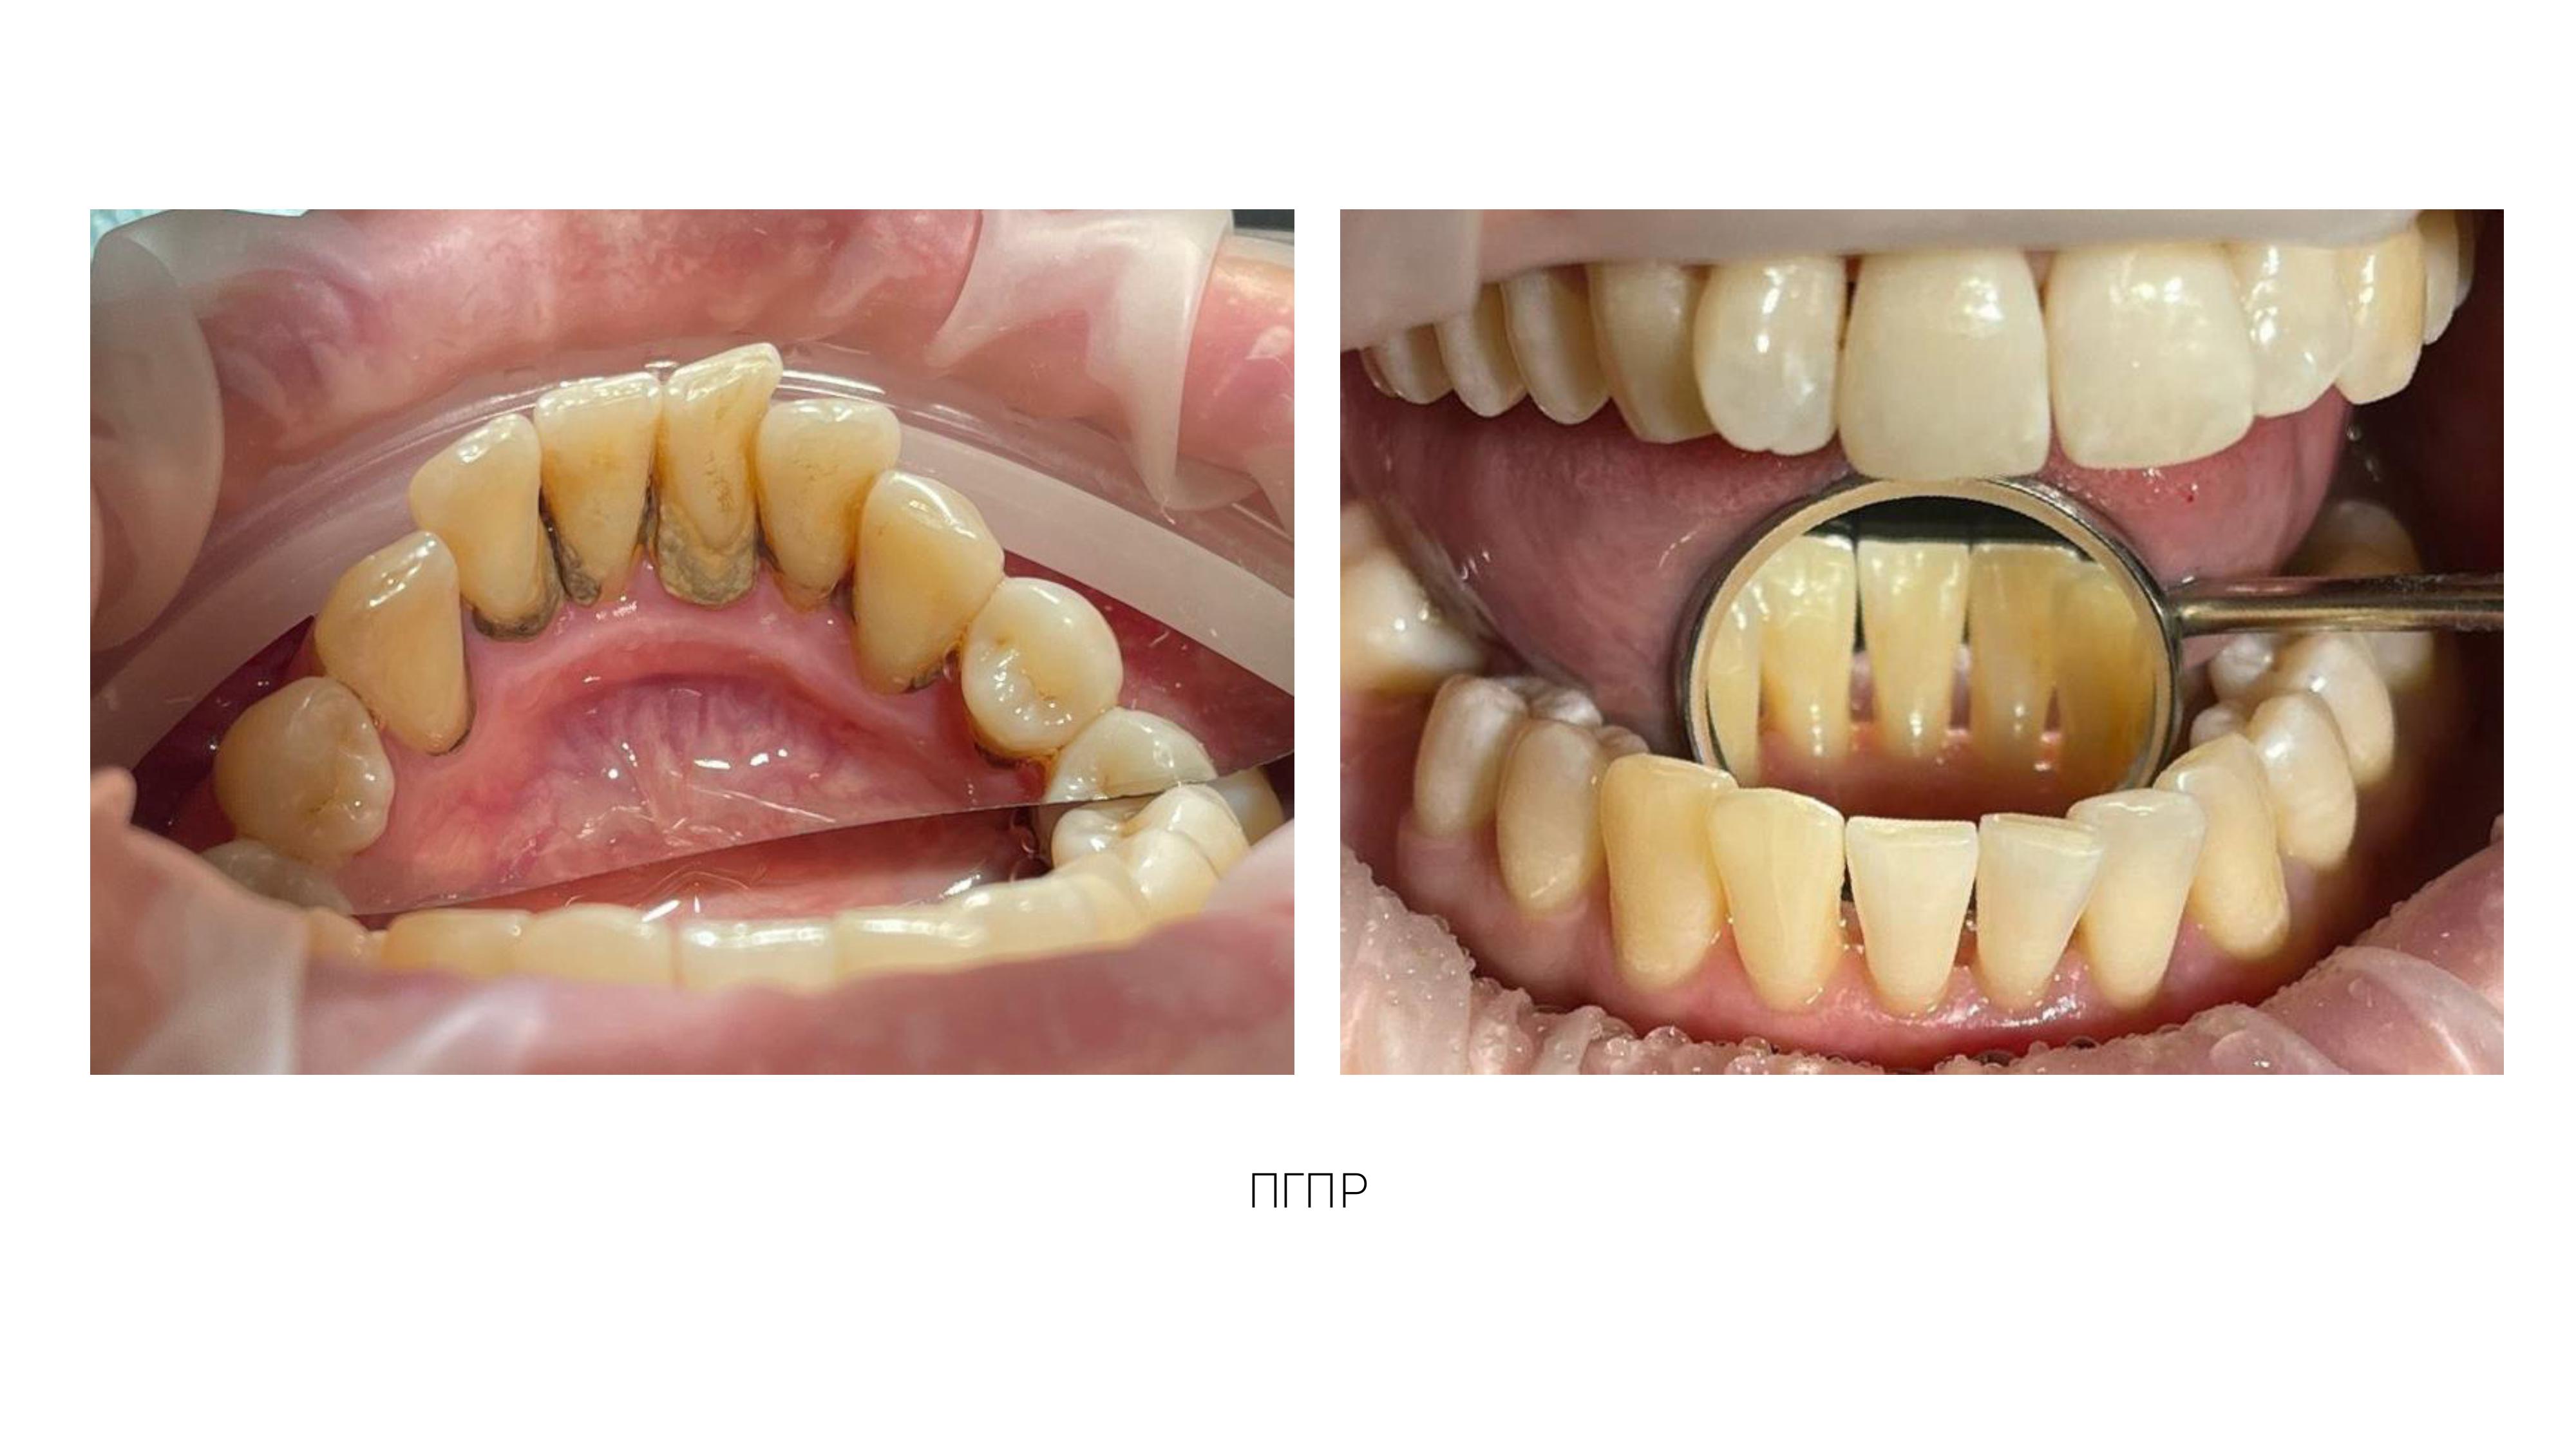

3. Профессиональная гигиена полости рта, фторирование, обучение и подбор предметов и средств по уходу за полостью рта.